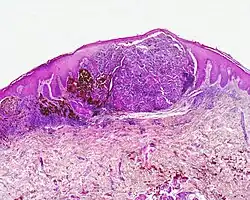

Czerniak podpaznokciowo-kończynowy

Czerniak podpaznokciowo-kończynowy. Rozrost atypowych melanocytów na granicy skórno-naskórkowej. W skórze nacieki zapalne, naskórek nadmiernie zrogowaciały

Jest to odrębna odmiana czerniaka występująca na dłoniach, stopach i podpaznokciowo z charakterystycznym obrazem histologicznym. Stanowi około 7–10% czerniaków[97][80][82]. Jednak jest znacznie częstszy u czarnoskórych i Azjatów, gdzie może być najczęstszą odmianą czerniaka w tych populacjach. Występuje głównie u starszych ludzi, częściej u mężczyzn[97]. Pojawia się w obrębie nieowłosionej skóry dłoni i stóp oraz podpaznokciowo. Niektóre definicje obejmują również grzbietową część dłoni. W 87% przypadków dotyczy stóp – w 57% jest zlokalizowany po stronie podeszwowej, 5% pod paznokciem i 9% po stronie grzbietowej. W 23% przypadkach pojawia się w obrębie dłoni – po stronie dłoniowej w 1%, grzbietowej w 9% i pod paznokciem w 14%[98]. Często dotyczy kciuka i dużego palca u stopy. Prawdopodobnie promieniowanie ultrafioletowe odgrywa w patogenezie czerniaka podpaznokciowo-kończynowego niewielką rolę[98].

Początkowo jest podobny do złośliwej plamy soczewicowatej. Wykazuje dwufazowy charakter wzrostu, początkowo o promienistym wzorcu wzrostu, następnie wzorzec pionowy. Klinicznie w fazie wzrostu poziomego występuje jako plamkowato nierównomiernie zabarwiona zmiana o nieregularnych, nierównych granicach. W fazie wzrostu pionowego w jej obrębie pojawiają się guzki. Częściej niż w innych podtypach występuje owrzodzenie[98].

Czerniak w obrębie paznokcia często zaczyna się jako plama pod paznokciem o odcieniu od brązowego do czarnego, często o smugowatej, pasmowatej pigmentacji. Dochodzi do pogrubienia, rozwarstwienia i zniszczenia płytki paznokciowej. Przebarwienie szerzy się z płytki paznokciowej na obrąbek naskórkowy lub opuszkę palca (objaw Hutchinsona)[29][98].

Mikroskopowo czerniak podpaznokciowo-kończynowy wykazuje charakterystyczny obraz histopatologiczny. W fazie promienistego wzrostu zmiana charakteryzuje się obecnością nadmiernego rogowacenia, poszerzenia warstwy rogowej naskórka, wydłużeniem listewek (sopli) naskórkowych i proliferacją atypowych melanocytów na granicy skórno-naskórkowej. Atypowe melanocyty są duże, zawierają powiększone jądra i dziwaczne jąderka, w cytoplazmie są obecne ziarnistości wypełnione melaniną. Rozprzestrzeniają się one w głąb skóry wzdłuż mieszka włosowego lub gruczołu potowego. W fazie pionowego wzrostu guz zawiera głównie komórki wrzecionowate, które są związane z reakcją desmoplastyczną (odczyn włóknisty)[99].